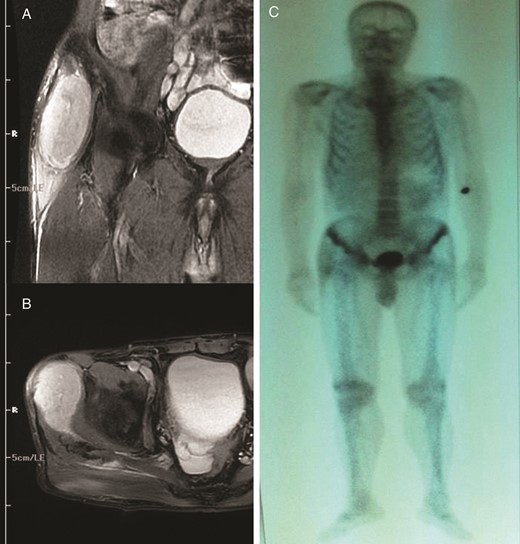

A 67-year-old man was admitted to our orthopedic clinic for a painful hard mass that had been slowly growing for >1 year at the posterolateral aspect of the right thigh. He had a 9-year history of left radical nephrectomy for a 6-cm diameter RCC (stage II [pT1 N0 Mx], nuclear grade Fuhrman grade III/IV). On physical examination, a 10 × 7 cm palpable mass was detected at the right posterolateral gluteal region. Magnetic resonance imaging (MRI) revealed a 165 × 75 × 67 cm hypervascular lesion within the gluteus maximus muscle, with unclear borders to the biceps femoris (Fig. 1A and B). After an incisional biopsy, the mass was reported as an RCC metastasis (Fig. 2A and B). Total excision of the mass was performed. Histochemical analysis of the total excision specimen revealed positive staining for cytokeratin, RCC and vimentin confirming the diagnosis. We performed a total body bone scan (Fig. 1C) to achieve complete stadiation of the mass. After complete healing, external radiotherapy was administered at 30 Gy to the right leg, in the surgical site, with an additional three cycles of immunotherapy regimen, including interferon-α (IFN-α), interleukin 2 and sunitinib therapy.

Coronal (A) and axial (B) T2-weighted fat-suppressed images showing the encapsulated soft tissue mass within the right gluteus maximus muscle; (C) whole-body bone scintigraphic image.